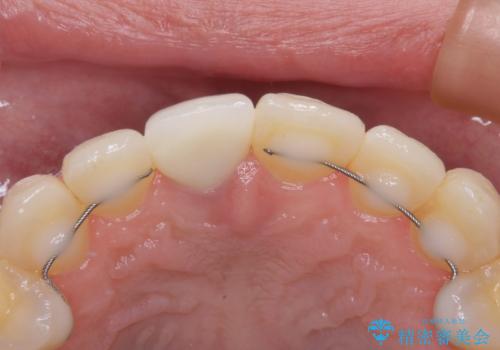

被せものと土台の歯との境目が、歯茎の下に隠れるように調整し、段差もないため、審美性・清掃性のどちらの観点からも理想的な被せものになり、患者様は満足されました。